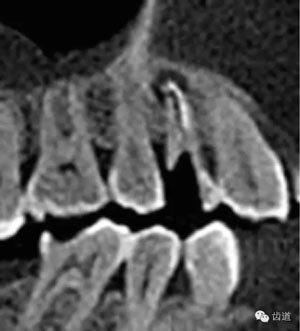

處理:顯微根管治療。放置橡皮障,去除暫封,顯微鏡下超聲去除頰側(cè)根管上段部分牙本質(zhì),探及遠(yuǎn)中根管口,見(jiàn)有糊劑遮蓋。Path file根管疏通,M Two根管預(yù)備至2506#,配合3%次氯酸鈉和17%EDTA超聲蕩洗,干燥根管,放置氫氧化鈣糊劑,zoe暫封。

術(shù)前CBCT檢查,根管顯微鏡結(jié)合超聲波治療儀的運(yùn)用。